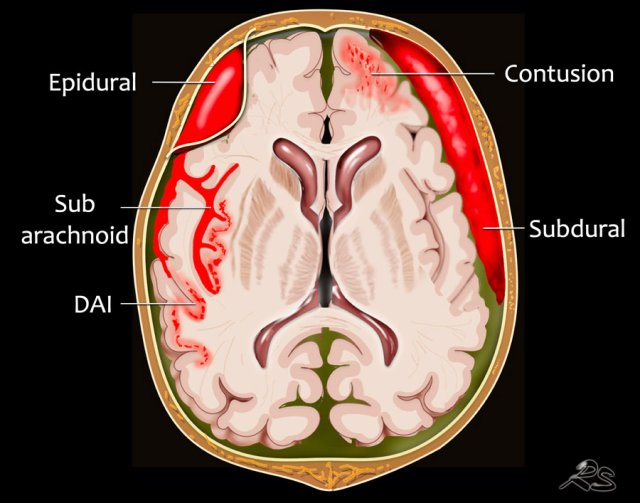

Localization of hemorrhage

Extra-axial hemorrhage - Intracranial extracerebral

• Subarachnoid hemorrhage is acute bleeding under the arachnoid. Most commonly seen in rupture of an aneurysm or as a result of trauma.

• Subdural hematoma is a bleeding  between the inner layer of the dura mater and the arachnoid mater of the meninges. It usually results from traumatic tearing of the bridging veins that cross the subdural space in patients with anticoagulantia therapy.

• Epidural hematoma is bleeding in the virtual space between the dura mater and the skull. Seen in fracture of the temporal bone with rupture of the middle meningeal artery.

Intra-axial hemorrhage - intracerebral

• Cerebral hemorrhagic contusion small post-traumatic hemorrhages located near the skull in the area of the coupe and contre-coup, most commonly frontobasal and anterior in the temporal lobes. Sometimes in combination with a subdural hematoma or subarachnoid hemorrhage.

• Diffuse axonal injury (DAI). Diffuse injury at the level of the gray-white matter junction seen in high velocity injuries. CT has low sensitivity. Better seen on MRI.